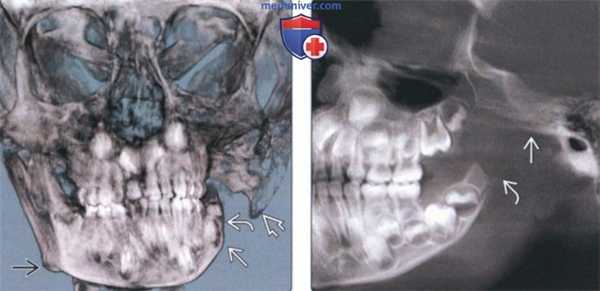

(Слева) На КЛКТ (объемный рендеринг) у девушки 16 лет с запущенной ПРМ определяется увеличение угла плоскости нижней челюсти. Углы нижней челюсти тупые, наблюдается задняя инклинация мыщелковых отростков. Подбородок смещен кзади и книзу. Вертикальные размеры передних отделов нижней челюсти уменьшены.

(Справа) На КЛКТ (вид спереди) у этой же пациентки определяется открытый передний прикус. Медиально-латеральные размеры альвеолярных отростков верхней и нижней челюсти уменьшены. Боковые отделы нижней челюсти недоразвитый. (Слева) На панорамной рекой струкции (КЛКТ) у этой же пациентки определяется укорочение мыщелкового отростка ветви. Антегониальная вырезка отчетливо выражена.

(Справа) На панорамной реконструкции нижней челюсти слева у этой же пациентки определяется задняя инклинация левою мыщелкового отростка. Задний край ветви вогнут сильнее, чем в норме. (Слева) На косой сагиттальной КЛКТ правого ВНЧС у этой же пациентки определяется выраженное уменьшение мыщелкового отростка. Задний край суставною возвышения уплощен и формирует пологий скат.

(Справа) На косом сагиттальном срезе левого ВНЧС у этой же пациентки наиболее выдающаяся точка заднею контура находится возле верхней поверхности мыщелка, что свидетельствует о приобретенном укорочении мыщелка за счет эрозивною процесса. Из-за маленькой суставной поверхности стрессовое воздействие на мыщелок при функциональных нагрузках выше.